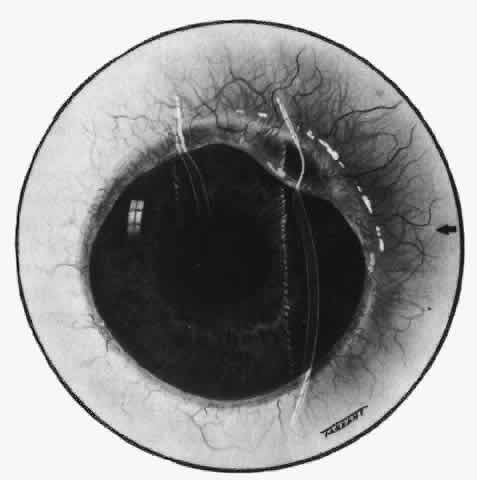

However, very large defects may have to be covered with sclera or cornea. Provided these grafts can be covered by conjunctiva, they usually remain in place, apparently viable. Scleral grafts ensure the comfort of the patient but do not prevent progressive necrotizing disease in the host sclera or even the graft (Figs. 63 and 64). Scleral replacement should be performed with the use of cornea rather than scleral tissue. Sclera rapidly resorbs, whereas corneal tissue is attacked only if there is a recurrence of the original disease.

Fig. 63. Severe necrotizing scleritis.

Fig. 64. Scleral graft in eye shown in Figure 63. Three months later the scleritis was still being treated with steroids. New vessels invaded the graft, which later took on the appearance of normal sclera.